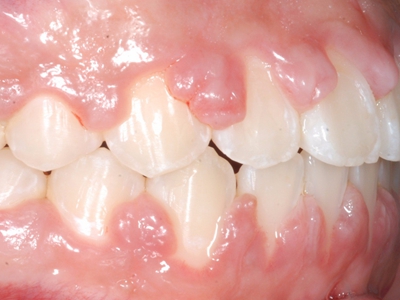

牙龈退缩牙龈萎缩露出牙根图

牙龈退缩发作于上排尖牙和磨牙处,导致牙根暴露在外,伴有牙齿松动、口臭、牙根面敏感等症状,是由于刷牙不当、牙周炎等因素引起。